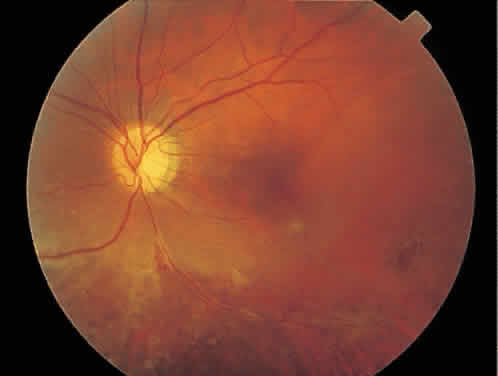

The hallmark lesion of CMV retinitis is a necrotizing, full-thickness retinitis that results in retinal cell destruction. CMV often initially affects retinal tissue adjacent to major retinal blood vessels or the optic disc (Fig. 1). This is consistent with the concept that the virus is spread to the retina hematogenously. In most cases, the pattern of infection is classic and distinctive, making clinical diagnosis straightforward. The area of active retinitis has a granular, dirty-white appearance. As the virus attacks the endothelial cells of blood vessels, hemorrhage is common. Advancement in the retinitis by both direct cell-to-cell transmission as well as spread by way of adjacent satellite lesions can be seen. Except for cases in which retinitis is acute, it is common to see areas of healed retinitis beside areas of active necrosis. Areas of burned-out necrosis show absence of any retinal tissue, whereas the underlying retinal pigment epithelium assumes a “salt and pepper” appearance. CMV retinitis can present initially as either large areas of retinal necrosis with hemorrhage or one or more small, focal areas of retinal whitening.1,12,14 These small, focal lesions may on occasion be confused with cotton-wool spots or lesions of toxoplasmosis.5,27 Unlike cotton-wool spots, focal areas of CMV may appear outside the posterior pole. These early, focal infiltrates of CMV may not be associated with retinal hemorrhages or vitreous cells.

Fig. 1. Typical appearance of peripapillary cytomegalovirus retinitis with hemorrhage and exudate. Despite the proximity to the optic nerve, the visual acuity was 20/20 (6/6) and the patient had no symptoms.